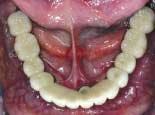

When the final restorations are received from the lab, they are inspected on the mounted models (figures 26 and 27). The final restoration is placed in the mouth and screwed in place. The access holes are filled with Clip, pink opaque composite and tooth-colored composite (figures 28 and 29). Final occlusal adjustments are made and esthetics confirmed (figure 30).